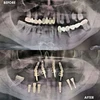

Implant tedavisi